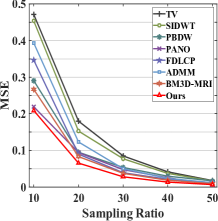

First, we test on 25 T1-weighted MRI data using three different undersampling patterns with a fixed 10% sampling rate. Fig. 3 shows the quantitative results (PSNR). Our method performances best for all three cases and has stronger stability compared with the second best method on variance. As for the effect of sampling ratios variation, we use radial mask under 10%, 30% and 50% sampling rates with evaluation of RLNE and MSE. Fig. 4 shows that our method has the lowest reconstruction error for all sampling rates. For more intuitive comparison, we illustrate the reconstruction error in term of pixels in Fig. 5. We also offer the qualitative comparison in Fig. 6. Visualized results demonstrate our method has better performance in both artifacts removing and details restoration. Time consuming is also considered. We compare our method with others on the 25 T1-weighted data using Radial mask with 10% and 50% sampling rate. Notice that ADMM-Net and ours are tested on GPU for the incorporation of deep architecture. Tab. 1 shows that our method provides an efficient reconstruction process and comes to the fastest method among the state-of-the-art competitors.